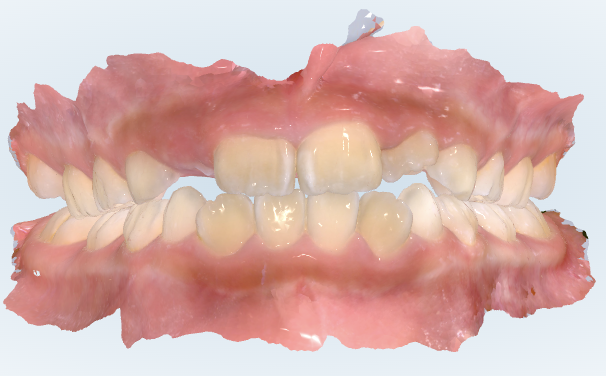

初診時の画像診断

上下の歯並びにガタガタがあります。

咬み合わせに出っ歯の傾向があります。